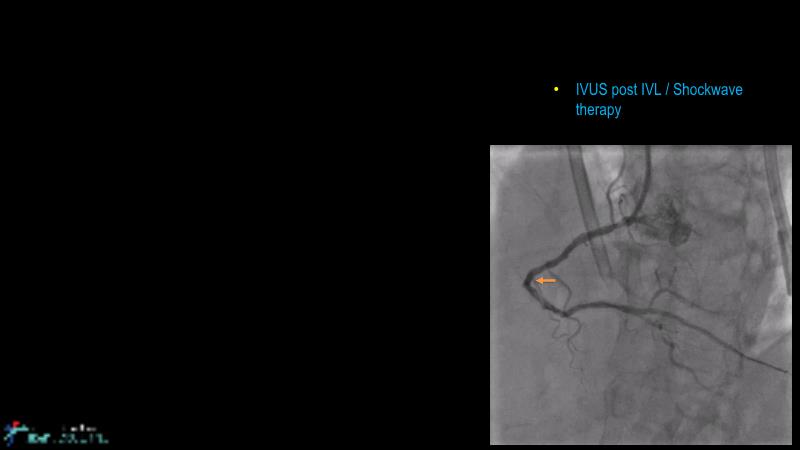

Cracking calcium: best practices to integrate intravascular lithotripsy into your calcium management algorithm

With this session, keep up to date on the evidence, trials and outcome data for intravascular lithotripsy in severely calcified lesions. Learn how to use this technique in real-world patients and understand its role in the treatment algorithm for severely calcified coronary lesions.